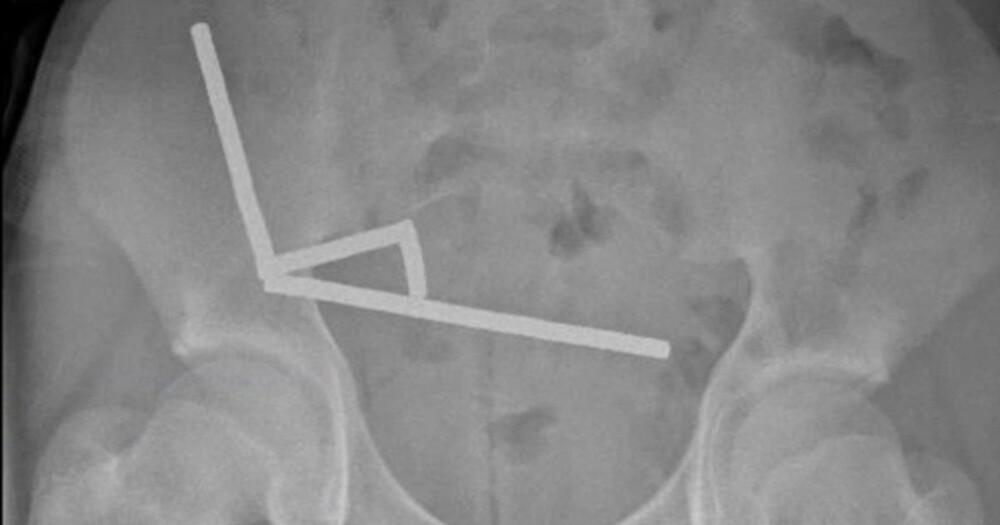

Подросток проглотил 100 магнитов и лишился части кишечника

Хирурги были поражены, обнаружив, что причина болей в животе у подростка — более ста мощных магнитов. В результате врачи новозеландской больницы в Тауранге провели экстренную операцию и удалили часть кишечника 13-летнего пациента.